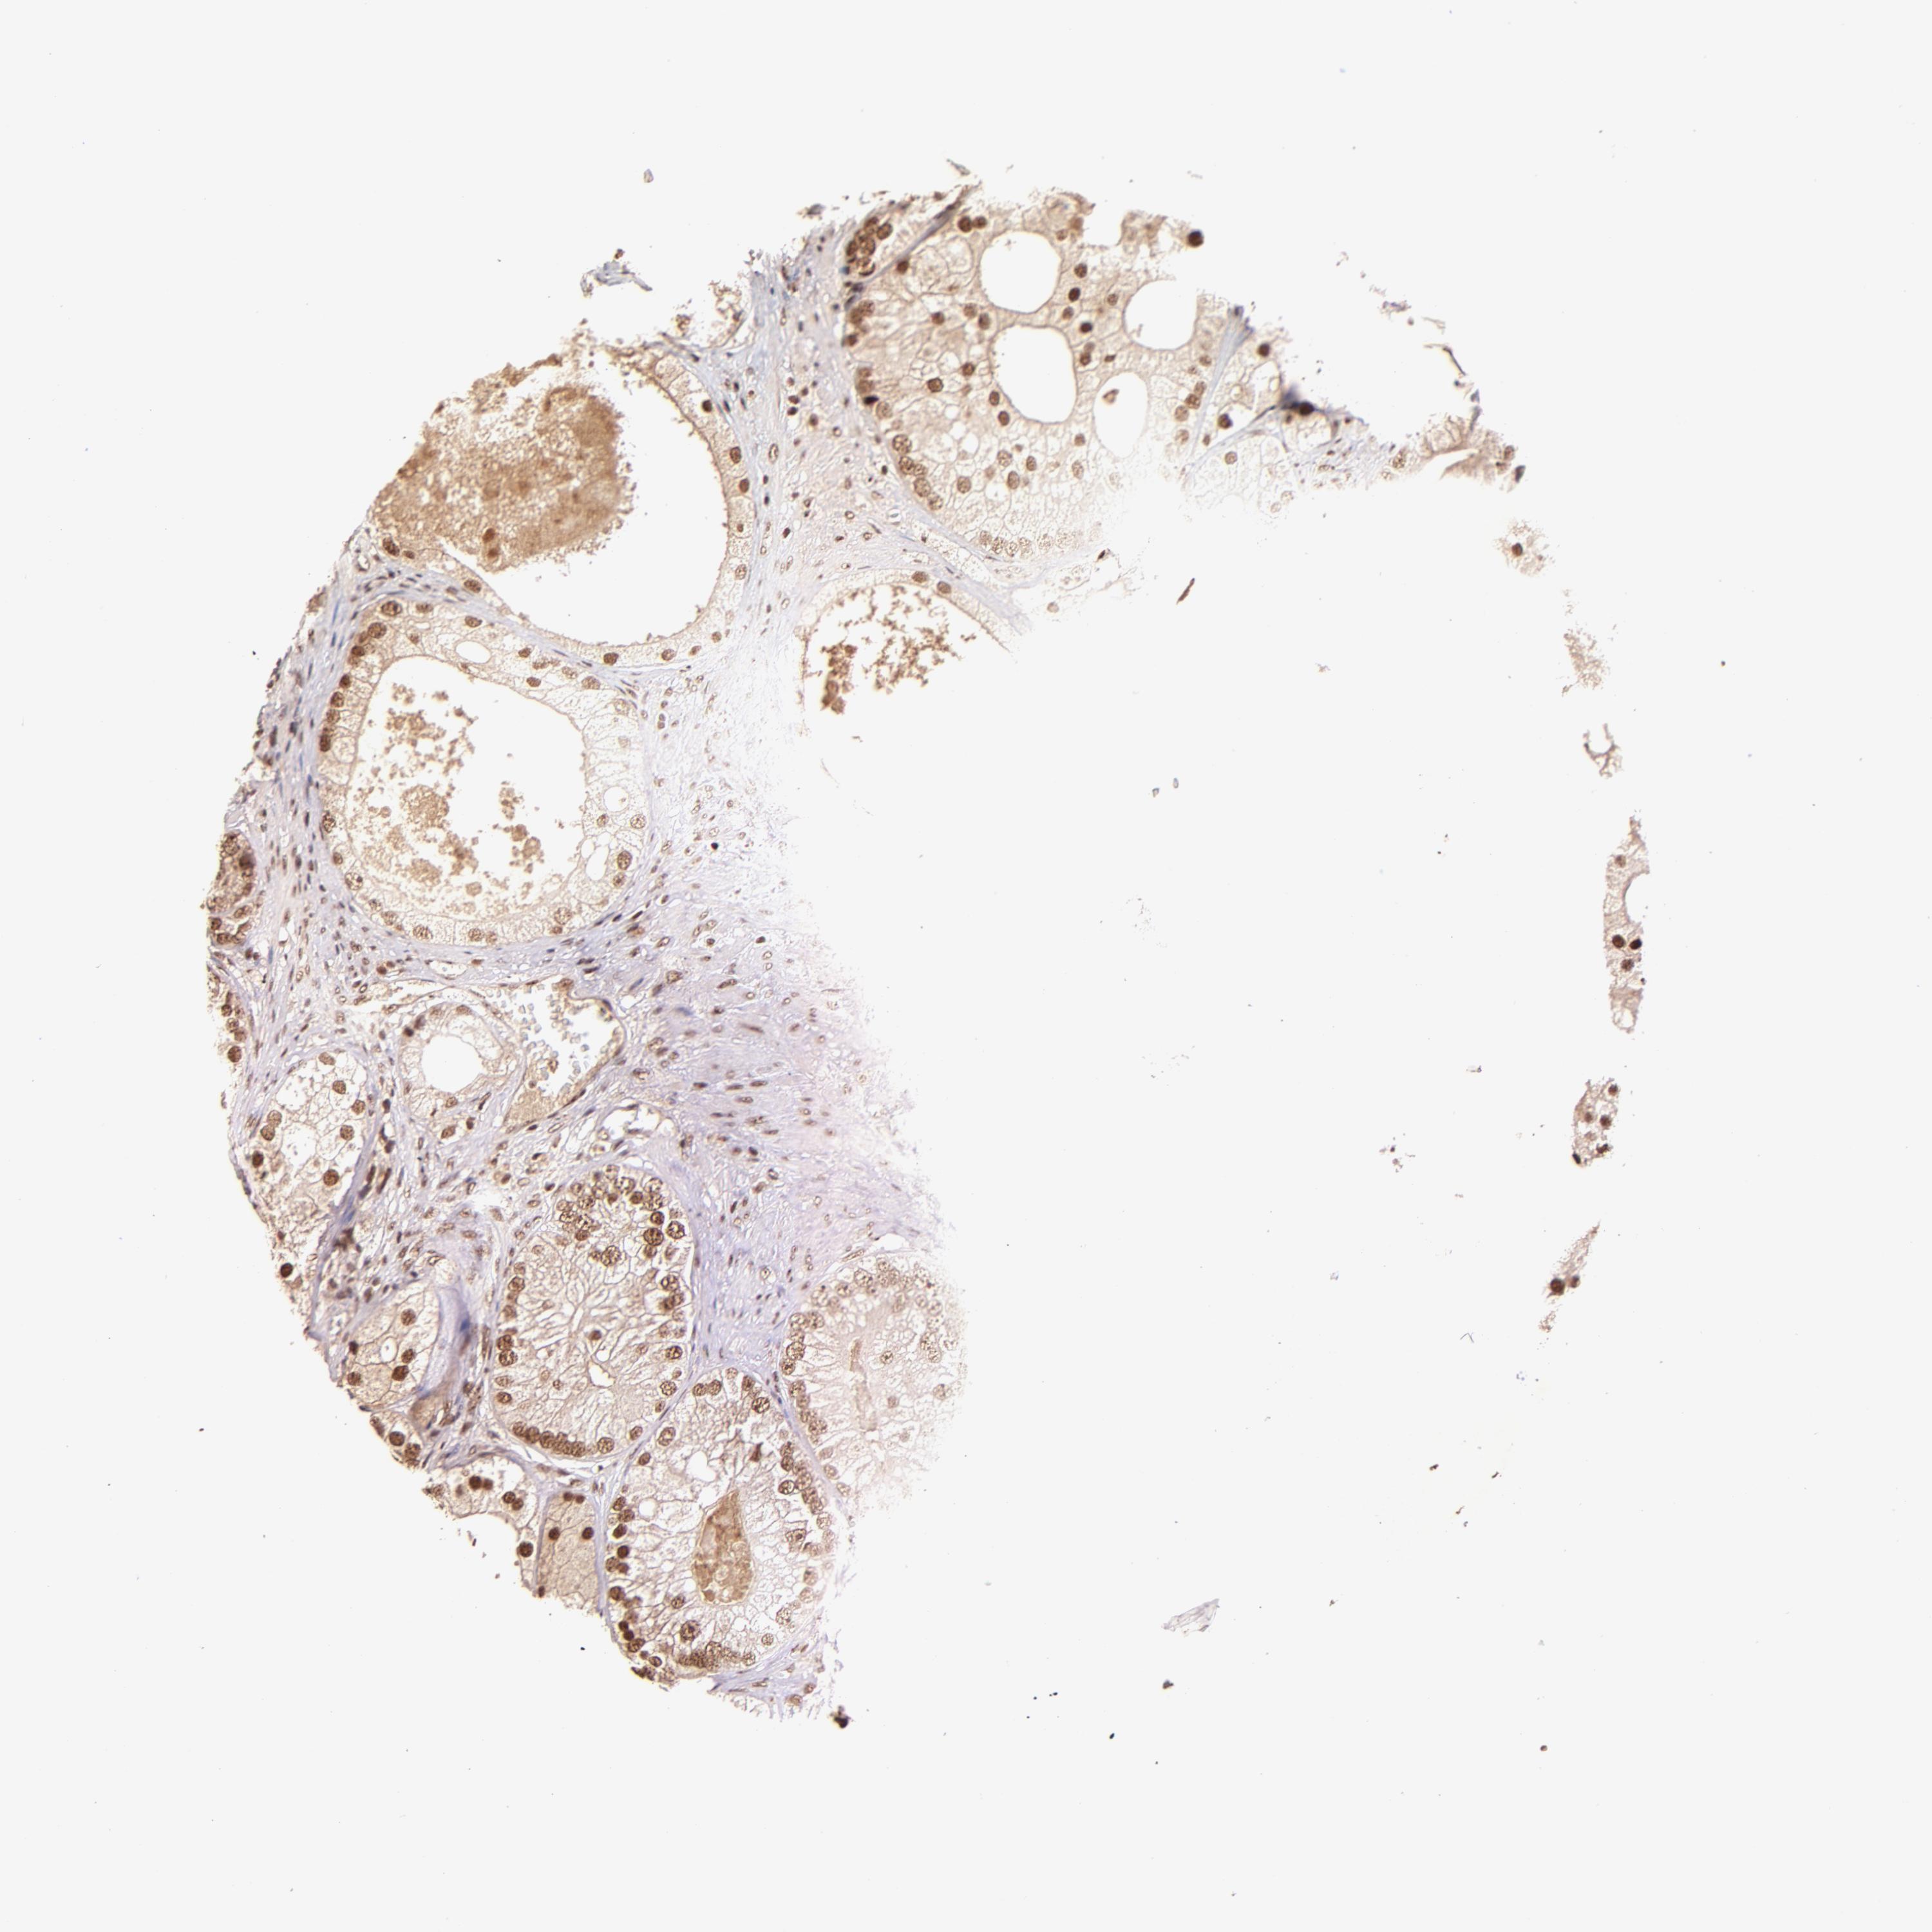

PROSTATE CANCER - Protein expressioni

A mouse-over function shows sample information and annotation data. Click on an image to view it in a full screen mode. Samples can be filtered based on level of antibody staining by selecting one or several of the following categories: high, medium, low and not detected. The assay and annotation is described here.

Antibody stainingi

Antibody staining in the annotated cell types in the current human tissue is reported as not detected, low, medium, or high, based on conventional immunohistochemistry profiling in selected tissues. This score is based on the combination of the staining intensity and fraction of stained cells.

Each image is clickable and will lead to virtual microscopy that enables deeper exploration of all samples and also displays staining intensity scores, fraction scores and subcellular localization as well as patient and tissue information for each sample.

Antibody HPA003184

Antibody HPA003185

Staining

High

Medium

Low

Not detected

Intensity

Strong

Moderate

Weak

Negative

Quantity

>75%

75%-25%

<25%

None

Location

Nuclear

Cytoplasmic/membranous

Cytoplasmic/membranous,nuclear

Adenocarcinoma, Low grade

Adenocarcinoma, Medium grade

Adenocarcinoma, High grade